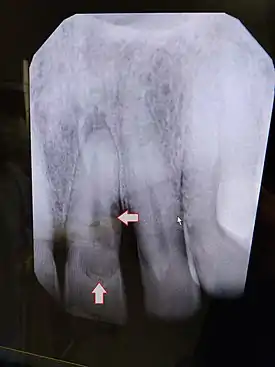

| Post traumatic External tooth resorption 9 | |

External inflammatory root resorption may be caused by trauma to the root surface, due to damage to the periodontal ligament (PDL) and/or extended drying following tooth avulsion. Following trauma, dentinal tubules are exposed leading to communication with an infective or necrotic pulp. This leads to an inflammatory process that causes external root resorption.[16]